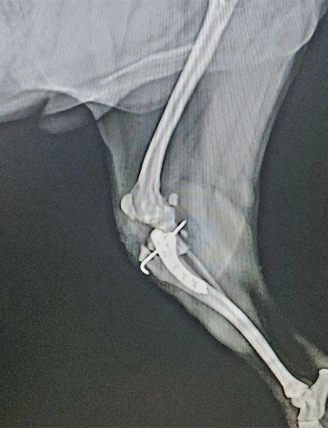

TPLO : Tibial Plateau Leveling Osteotomy

강아지 후지파행의 한 원인인 전십자인대 단열의 경우에 시행하는 수술로서 최근 낭외재건술보다 우선 선택되는 수술법입니다.